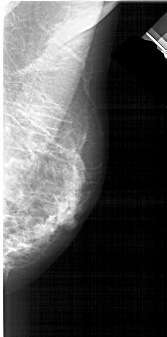

A_1938_1.RIGHT_MLO

LEFT_MLO LINES 5101 PIXELS_PER_LINE 2506 BITS_PER_PIXEL 12 RESOLUTION 43.5 OVERLAY